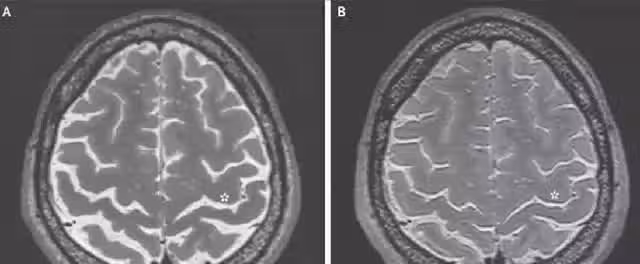

這些影響有可能導致認知能力下降,身體衰老速度加快,反應遲緩等等。綜合起來,太空人的大腦是否會出現明顯的萎縮現象,是不能絕對否定的。

對於某些航天員的腦部檢查報告顯示,在他們返回地球後的一段時間裡,身體的健康狀況的恢復還是比較緩慢。對於一些太空人定期的檢查,發現了大腦腦脊液的分布變化,並沒有回歸正常。

因此有科學家認為,長期處於太空失重環境下,太空人大腦發生病變的幾率也會增大。